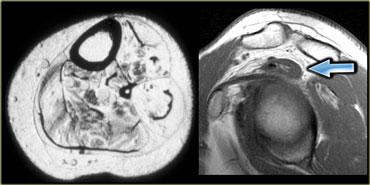

Cơ khuỷu trên ròng rọc phụ (mũi tên đỏ) – Thần kinh trụ tăng tín hiệu gợi ý viêm thần kinh trụ (mũi tên xanh)

Hình bên trái là hình ảnh khớp khuỷu, mặt trong nằm ở bên trái.

Lưu ý có một cơ nằm ngay phía sau thần kinh trụ, trong điều kiện bình thường cơ này không hiện diện tại vị trí này.

Đây là cơ khuỷu trên ròng rọc phụ (accessory anconeus epitrochlearis), gặp ở khoảng 10% dân số.

Đây là nguyên nhân thường gặp gây viêm thần kinh trụ do chèn ép, biểu hiện bằng đau và tê bì mặt trụ của bàn tay, đôi khi kèm teo cơ mô út và mô cái.

Cần quan sát kỹ thần kinh trụ khi phát hiện cơ phụ này.